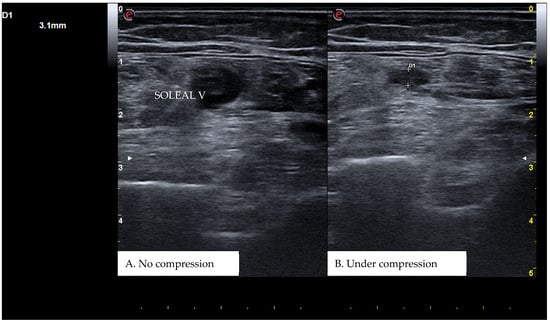

CUS is a diagnostic technique primarily designed to find DVT by checking the veins’ compressibility with the principle that healthy veins are normally compressible and would collapse under the pressure of the ultrasonographic probe. In the case of the presence of a venous thrombus, the vessel would not be able to collapse under such pressure [8,9]. Linear high-frequency transducers are generally used for CUS as they best visualize leg veins [10]. The ultrasound machine settings must be adjusted carefully in order to limit possible operator-related bias. Important elements to be considered in this setting include gain, focus, and time-gain compensation. Gain adjustment regulates image brightness, focus optimization sharpens the image to the desired depth, and time-gain compensation enhances the visibility of subtle echoes, ensuring uniform image quality [10,11]. The transducer partially compresses the vein, which creates an echogenic response. In normal veins, this technique should fully compress the lumen [9]. However, with thrombosis present, the vein does not collapse enough, which causes a non-continuous echogenic line [12]. While the femoral veins are usually well identified in the groin and thigh areas, to facilitate better visibility of the popliteal veins, the patient may lie in a supine position with the leg slightly abducted to relax the muscles or, alternatively, in a prone position [9]. Real-time B-mode and Doppler imaging are both valuable tools in this process. B-mode imaging can find incomplete vein collapse during compression [13,14]. Doppler imaging can show the thrombus or find a complete lack of flow in the lumen [9]. As such, CUS for DVT diagnosis involves evaluating direct signs like the presence of a non-compressible echogenic line suggesting a thrombus, as well as indirect signs like changes in vein compressibility and thrombus echogenicity [6,7]. In addition, evaluation of flow patterns and flow response during augmentation maneuvers may refine the diagnostic examination, although their implementation requires more advanced training and skills than simple CUS [7]. Clinicians should assess a spectrum of veins, including the external iliac, common femoral, superficial and deep femoral, popliteal, tibial, peroneal, gastrocnemial, and soleal veins, as well as the junctions with the great and small saphenous veins, representing the superficial systems [15]. Challenges exist in visualizing the iliac veins, especially in obese patients, yet phasic flow in the femoral veins can be indicative of DVT status, particularly for excluding iliac vein thromboses [16]. This comprehensive approach is standard in differentiating healthy veins, which should collapse and enlarge with augmentation maneuvers, from those with thrombosis, which show impaired response to pressure and flow changes [12,17]. Figure 1, Figure 2, Figure 3 and Figure 4 show real examples of DVT affecting different sites of the lower limb deep venous system, diagnosed through a CUS modality.

Figure 4. A real example of soleal vein thrombosis at the level of the right distal popliteal region. D1 shows the residual diameter of the non-compressible vein (i.e., the maximum diameter of the relative venous thrombus).